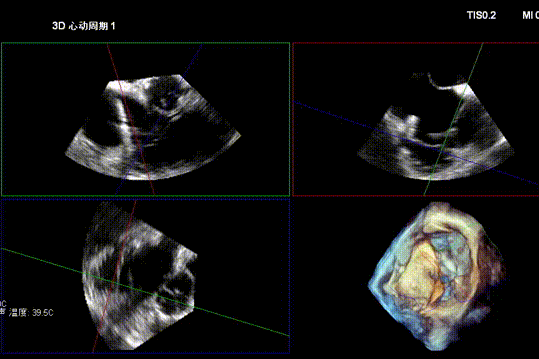

After general anesthesia, the patient underwent jugular vein puncture to establish access. An 18Fr delivery sheath was advanced over a super-stiff guidewire to the mid-to-lower right atrium. Under ultrasound guidance, the delivery system was introduced. A 14T K-Clip® and a 16T K-Clip® device were implanted at the postero-septal commissure annulus and the antero-posterior commissure annulus, respectively. The angle between the device and the annular plane was adjusted through controlled flexion and rotation to orient the device tip toward the target site. Using ultrasound MPR mode, the anchor component was advanced into the annulus. After traction confirmed stability, the clip arms were opened and apposed to the annulus. The anchor component was then retracted to close the clip arms, achieving annuloplasty. The effect was evaluated as satisfactory, and the clip components were deployed.

Opening clip arms, adjusting orientation, and apposing to the annulus

Closing the clip and evaluating effect under ultrasound